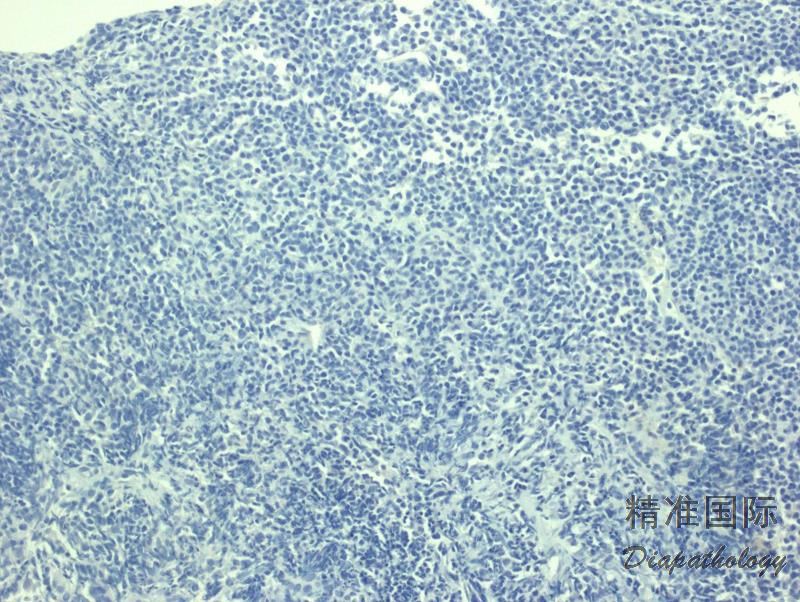

- 外周血可见循环肿瘤细胞和红细胞成钱串样重叠;骨髓几乎总是受侵犯,非小梁旁或小梁旁, 间质或弥漫侵润;淋巴结受侵以副皮质区为明显,可累及整个淋巴结。肿瘤细胞由小淋巴细胞、浆淋巴细胞和浆细胞谱系组成,可见 Dutcher 或 Russell 小体。肥大细胞数增加。